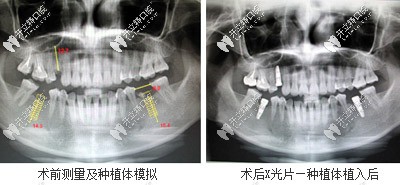

一、數(shù)字化影像三維重建+雙重掃描 ?——采用德國(guó)西諾德、普蘭梅卡診療系統(tǒng)、數(shù)字化斷層掃描準(zhǔn)確測(cè)量牙槽骨寬度、高度、厚度,給種植體植入深度、角度更有保障。

數(shù)字化影像三維重建